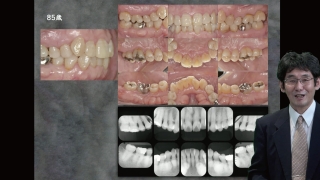

う蝕、歯周病のメインテナンスに取り組む診療室も増加し、患者側からの認知も高まってきて、今回の診療報酬改定でも長期的管理について、一定の報酬が割り付けられた。しかし、実際に提供されているメインテナンスの内容は多様で、メインテナンス希望で当院に初診に来院した患者の中には、前医で十分な満足が得られなかったというケースも散見される。今回は、疾患の特性に基づいて、どのようなメインテナンスを提供すればいいのかについて考察したい。合わせて医院運営上の問題についても少し触れてみたいと思う。